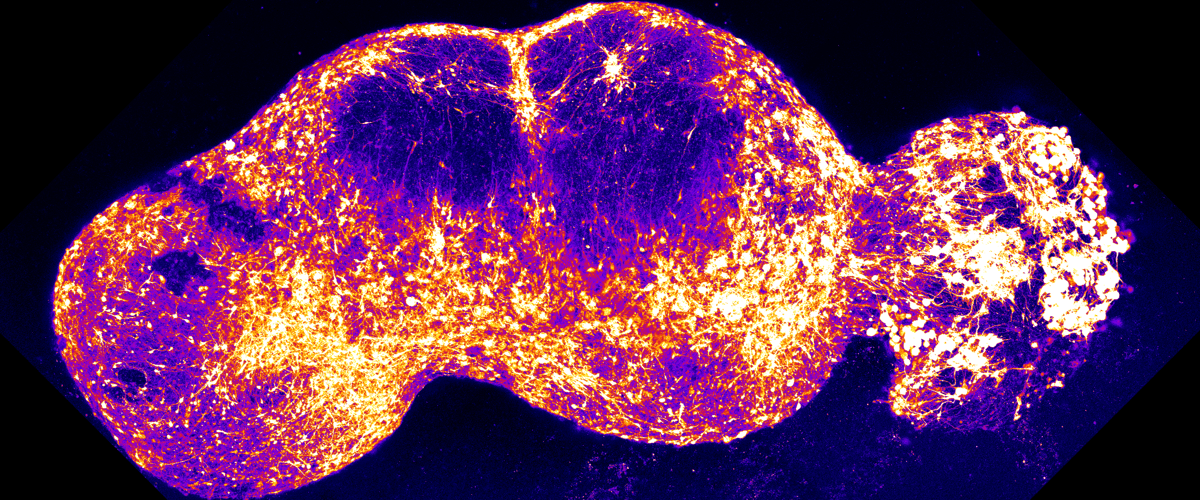

Ученые разработали «сенсорный ассемблоид» — комбинацию из двух и более органоидов, представляющую собой модель болевого пути. Для ее создания клетки кожи человека были перепрограммированы в стволовые клетки. Из этих стволовых клеток исследователи вырастили мини-органы, имитирующие ключевые структуры нервной системы, участвующие в восприятии боли: спинальный ганглий, спинной мозг, таламус и соматосенсорную кору.

Разместив эти органоиды рядом, исследователи три месяца наблюдали, как нейроны из одного кластера прорастали в другой и формировали рабочие нейронные цепи. Стимуляция органоида, представляющего кожные сенсорные нейроны, вызывала электрический импульс, который распространялся по всей цепочке органоидов, подобно тому, как это происходит в нервной системе живого человека.

Для проверки модели команда использовала капсаицин — молекулу, которая придает перцу чили жгучесть. Как и в организме, это вызвало каскад нервных импульсов, зафиксированных методами кальциевой визуализации и электрофизиологии. Сигналы проходили через все четыре мини-органа с определенным ритмом, напоминая обработку сенсорной информации в настоящем мозге. При сравнении ассемблоидов с изолированными органоидами стало очевидно, что только собранная модель демонстрировала последовательное распространение активности по всем четырем областям.